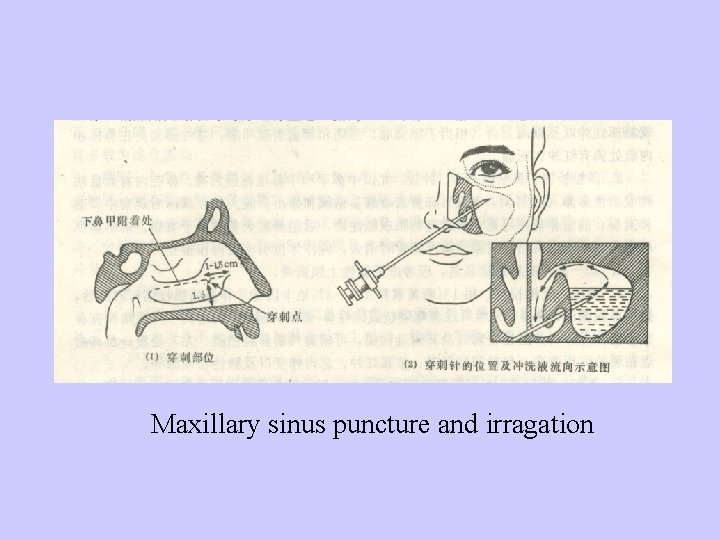

Treatment:Eradicate causes,keep drainage; control infection and prevent complications 1、General treatment:take rest,antibiotics, antihistamine (if necessary ) 2、Local treatment 3、Body drainage 4、Physical therapy 5、 Puncture and irrigation of maxillary sinus

Maxillary sinus puncture and irragation